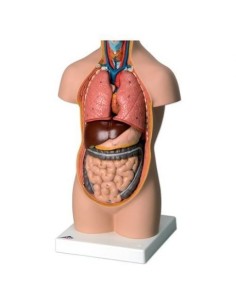

Scopri il Mondo dell’Anatomia con Modelli anatomici di Precisione

Modelli Anatomici Dettagliati per Ogni Necessità

Dal cranio in 22 parti con incastri magnetici ai modelli di colonna vertebrale, da quelli di articolazioni a quelli di cuore, ogni pezzo della nostra collezione è progettato per un’immersione totale nello studio dell’anatomia umana. I nostri modelli, realizzati tramite scansioni di ossa vere, garantiscono un’esperienza tattile autentica e una fedeltà di peso quasi identica agli originali.

Strumenti Didattici Innovativi per l’Educazione e la Pratica Medica

Essenziali per studenti e professionisti, i nostri modelli anatomici sono strumenti didattici che permettono di osservare le strutture anatomiche con precisione, eliminando la necessità di dissezioni o studi invasivi. Sono inoltre utili per spiegare ai pazienti le patologie, rendendo la comunicazione più efficace e risparmiando tempo prezioso.